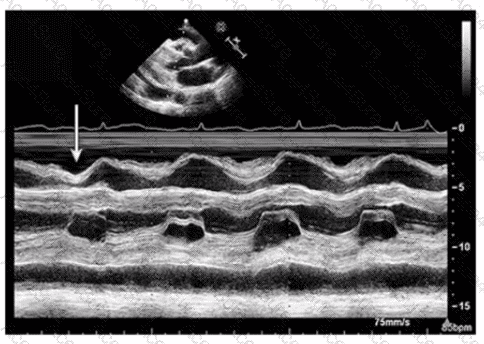

Which condition is most plausible based on the finding indicated by the arrow on this image?